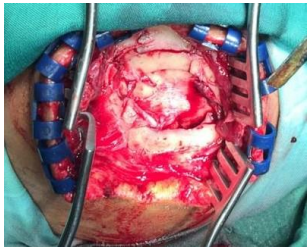

Fig 8 &9 Skull haemangioma (pre- and post-operative craniectomy with excision of the tumour)

Fig 10: Cranioplasty with mesh and acrylic bone cement

Fig: 11,12: Cranioplasty with auto graft and acrylic bone cement